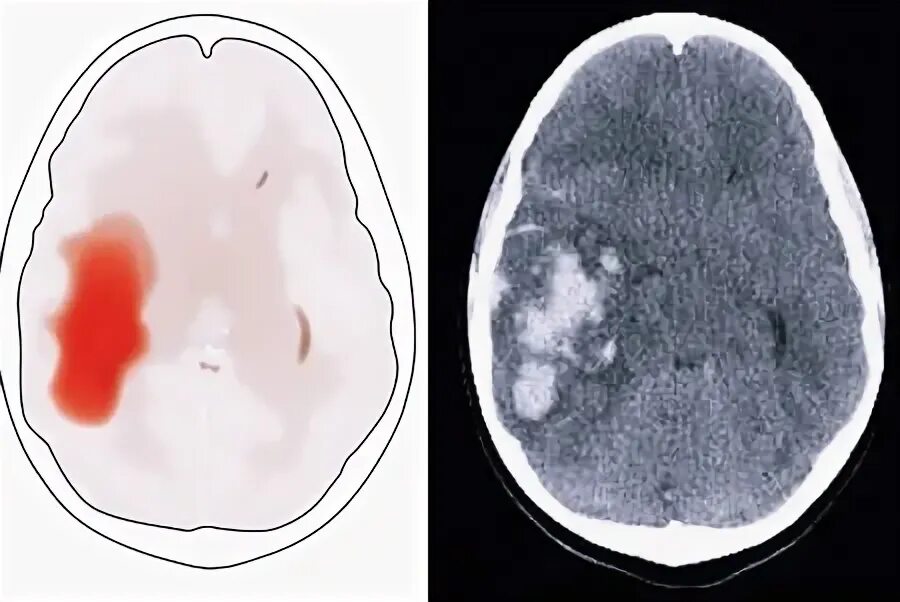

Кровоизлияние в мозг симптомы. симптомы кровоизлияния.Кровоизлияние в мозг диагноз. кровоизлияние в мозг причины. клинические проявления кровоизлияния в мозг. фактор риска кровоизлияния в мозг.Геморрагический инсульт симптомы. геморрагический инсульт проявления. мозговое кровоизлияние симптомы. признаки геморрагического инсульта.Геморрагический инсульт разрыв сосуда. геморрагический инсульт сосуд разрывается. геморрагический инсульт головного мозга. факторы возникновения геморрагического инсульта.Кровоизлияние в мозг симптомы. кровоизлияние в мозг причины признаки. кровоизлияние в мозг это инсульт. кровоизлияние в головной мозг причины.Кровоизлияние в мозг патогенез. морфогенез кровоизлияния в мозг.Геморрагический инсульт. обширное кровоизлияние.Кровоизлияние в мозг симптомы первые признакиКровоизлияние в мозг симптомы первые признакиКровоизлияние в мозг симптомы первые признакиКровоизлияние в мозг симптомы первые признакиСимптомы внутреннего кровотечения головного мозга. кровоизлияние в мозг это инсульт. разрыв патологически измененного кровеносного сосуда.Кровоизлияние в желудочки головного мозга. вентрикулярный геморрагический инсульт. геморрагический инсульт внутримозговое кровоизлияние.Кровоизлияние в мозг симптомы первые признакиГеморрагический инсульт разрыв сосуда. геморрагический инсульт сосуд разрывается. кровоизлияние в головной мозг. кровоизлияние в мозг геморрагический инсульт.Внутримозговое кровоизлияние. внутримозговое кровоизлияние инсульт. внутримозговая гематома. внутримозговые кровоизлияния возникают:.Кровоизлияние в головной мозг. субарахноидальное кровоизлияние в мозг.Эпидуральная гематома головного мозга. субдуральная гематома и субарахноидальное кровоизлияние. эпидуральное кровоизлияние в головной мозг. эпидуральная субдуральная и субарахноидальная.Кровоизлияние в мозг симптомы первые признакиУкажите исход гематомы в головном мозге:. гематома головного мозга симптомы. спазмы головного мозга симптомы. спазм сосудов головного мозга симптомы.Кровоизлияние в мозг геморрагический инсульт. кровоизлияние в мозг симптомы. кровоизлияние в мозг осложнения.Геморрагический субарахноидальный инсульт. геморрагический инсульт головного мозга. кровоизлияние в головной мозг. ишемический и геморрагический инсульт головного мозга.Геморрагический инсульт головного мозга. геморрагический церебральный инсульт. острое нарушение мозгового кровообращения ишемический инсульт. онмк геморрагический инсульт симптомы.Кровоизлияние в мозг симптомы первые признакиИнсульт кровоизлияние.Кровоизлияние в мозг симптомы первые признакиОстрое нарушение мозгового кровообращения (онмк). внутримозговое кровоизлияние. острое нарушение кровообращения. клиническая картина онмк.Кровоизлияние в мозг симптомы первые признакиКровоизлияние в мозговом желудочке. кровоизлияния в мозговой ткани. внутримозговой геморрагический инсульт. аневризма головного мозга операция инсульт.Гематомы головного мозга классификация. пластинчатая субдуральная гематома головного мозга. виды травматических внутричерепных гематом по локализации. внутричерепная родовая травма эпидуральные кровоизлияния.Кровоизлияние в мозг симптомы первые признакиНетравматическое субарахноидальное кровоизлияние. субарахноидальное кровоизлияние кт. плоскостные кровоизлияния. исход кровоизлияния в головной мозг.Этиология внутримозгового кровоизлияния. внутримозговое кровоизлияние причины. кровоизлияние патогенез. патогенез внутримозгового кровоизлияния.Нарушение мозгового кровообращения. нарушение головного мозга. нарушение кровоснабжения. нарушение кровоснабжения головного мозга.Субарахноидальное кровоизлияние схема. субарахноидальное кровоизлияние мрт. внутрижелудочковые кровоизлияния геморрагический инсульт.Геморрагический инсульт причины. геморрагический инсульт разрыв сосуда. кровоизлияние в мозг геморрагический инсульт. геморрагический инсульт мозг.Геморрагический инсульт разрыв сосуда. онмк геморрагический инсульт симптомы. карта геморрагический инсульт. геморрагический инсульт причины.Кровоизлияние в мозг симптомы первые признакиПатогенез геморрагического инсульта. кровоизлияние в головной мозг. ишемический и геморрагический инсульт головного мозга.Внутреннее кровотечение черепное. симптомы кровоизлияния в мозг симптомы.